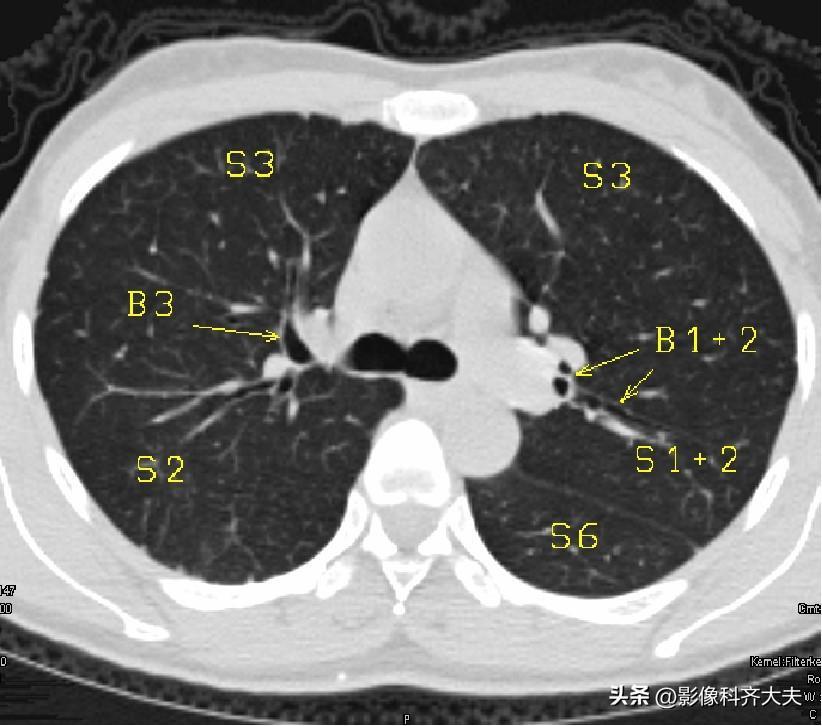

图5-近隆突层面

▲B1+2:左上叶尖后段支气管B3:上叶前段支气管